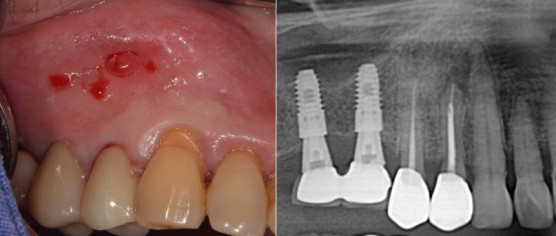

#14 뿌리 밑 염증, fistula 발견

이미지